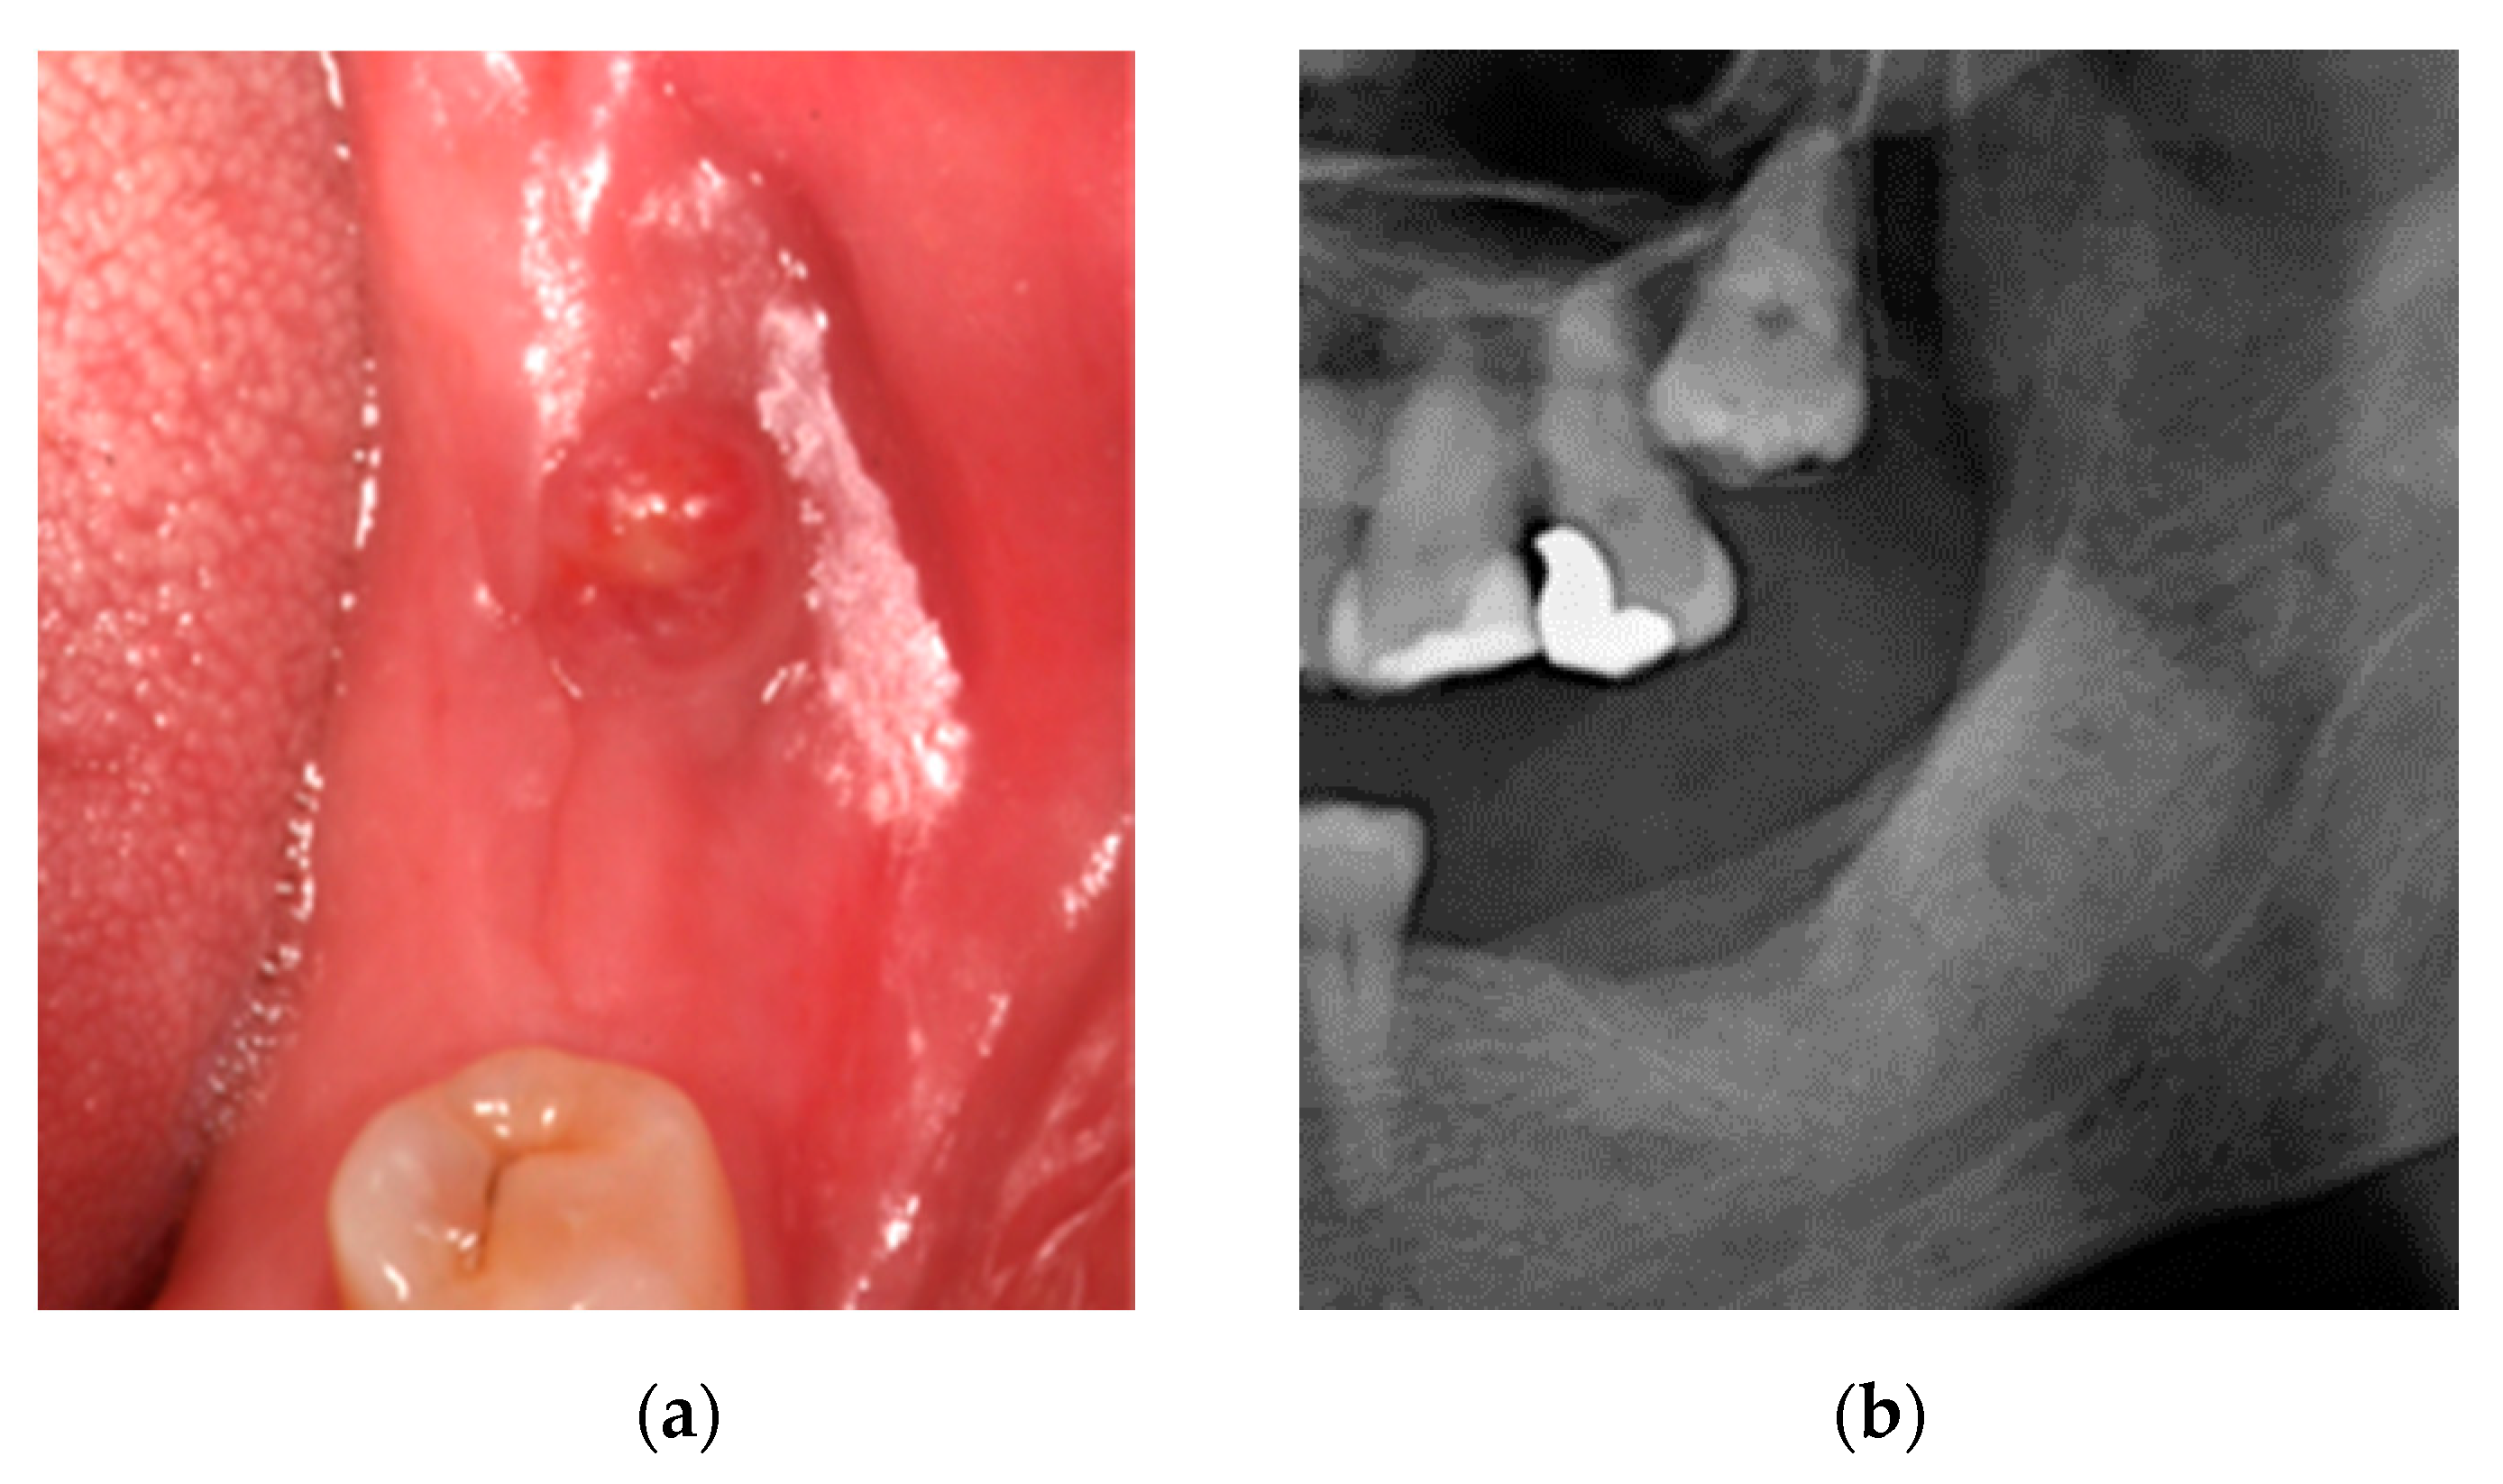

2.2. Case 2: Conservative Treatment Plus Surgery

2.3. Case 3: Conservative Treatment + SURGERY + PRF-L